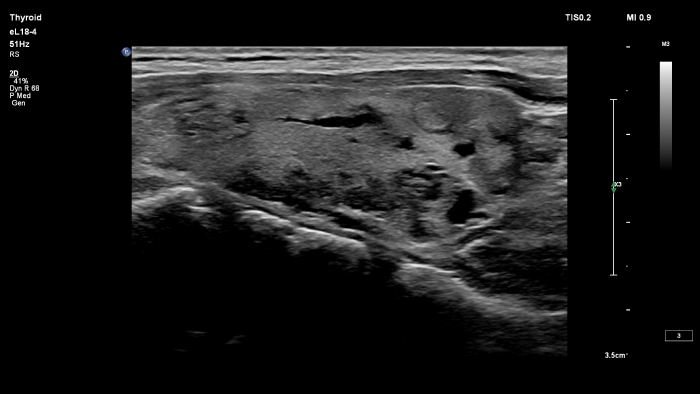

O transdutor PureWave eL18-4 da Philips inclui matrizes de cristais multilinhas que proporcionam imagens de corte fino para uma excecional resolução dos detalhes, ao mesmo tempo que fornece imagens e penetração extraordinárias.